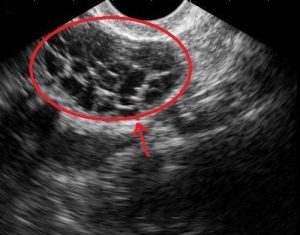

Die meisten Symptome sind nur schwach und lassen innerhalb einer Woche nach. Dennoch müssen alle Fälle streng überwacht werden, falls ein Eingriff erforderlich wird. Betroffene sollten sich zweimal pro Tag wiegen, um eine abrupte Gewichtszunahme zu erkennen. Zudem sollten sie auch ihre Harnausscheidung im Auge behalten. Bei plötzlichen Änderungen ist in jedem Fall umgehend ein Arzt zu konsultieren, der Untersuchungen wie einen Vaginalultraschall vornimmt, um Schwellungen der Eierstöcke sowie mögliche Zysten zu beobachten. Zudem werden Bluttests gemacht, um sicherzustellen, dass die Nieren richtig funktionieren. Zur Vermeidung von Blutgerinnseln in den Beinen sollten Kompressionsstrümpfe getragen werden.